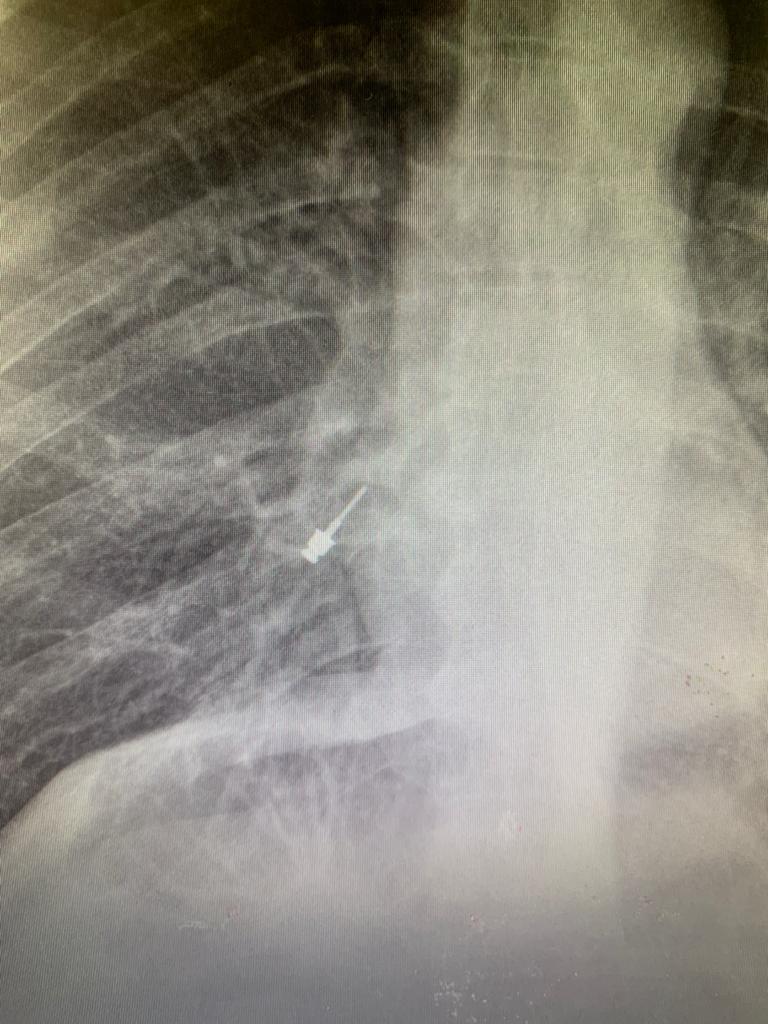

תוך כדי הטיפול, נשאף מברג השתלים לתוך קנה הנשימה של המטופל שלא הרגיש כלל בכך במהלך הטיפול אך לאחריו סבל משיעול קל. צילום חזה שבוצע לימד על כך שהמברג נשאף לריאה הימנית של המטופל ובשל הממצא המסוכן, פונה המטופל בדחיפות למרכז הרפואי שערי צדק.

החולה טופל על ידי צוות מכון הריאה בבית החולים שערי צדק. תחת הרדמה כללית הוחדר דרך קנה הנשימה מכשיר ברונכוסקופ. בקצה המכשיר מצלמת וידאו שדרכה אותר המברג כשהוא תקוע בתוך הסמפון לריאה הימנית התחתונה. דרך הברונכוסקופ הוחדר מכשיר נוסף שבקצהו לולאה. הצוות הידק את הלולאה סביב המברג ושלף את המברג החוצה.